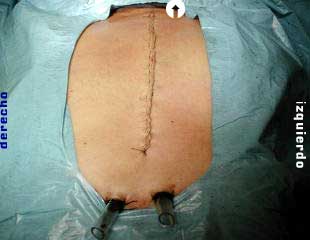

Aspecto post operatorio de la esternotomia, dos tubos pleuromediastinales gruesos, uno en cada hemitorax, esteriorizados por contrabertura en el epigastrio, se conectan a sistema de drenaje torácico para drenaje pleuromediastino y expansión pulmonar.